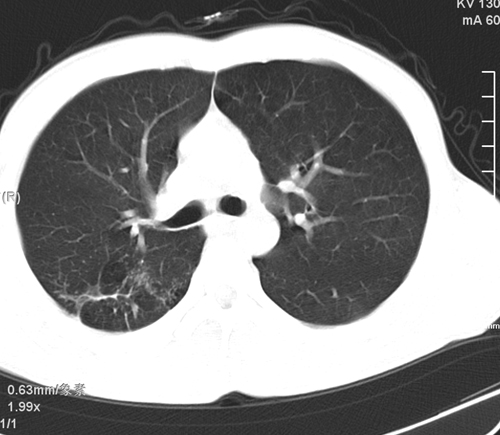

标题: CT24548:男 31 咳嗽 咯血一天 行CT检查 [打印本页]

标题: CT24548:男 31 咳嗽 咯血一天 行CT检查

ct考虑结核 但化验结果示白细胞总数 淋巴均正常,血沉7mm/h不快,请看看结核 支扩还是其他

右肺上叶尖端,后段下叶背段结核伴空洞形成

好发部位+多种性质病灶=典型tb